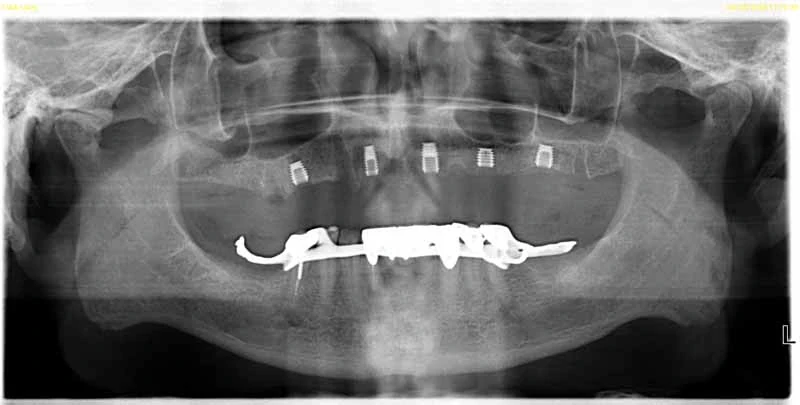

Dental Implant Gallery